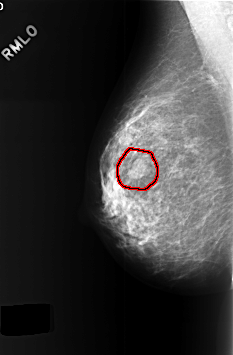

C_0377_1.RIGHT_MLO

RIGHT_MLO LINES 5680 PIXELS_PER_LINE 3728 BITS_PER_PIXEL 12 RESOLUTION 50 OVERLAY

FILE: C_0377_1.RIGHT_MLO.OVERLAY

TOTAL_ABNORMALITIES 1

ABNORMALITY 1

LESION_TYPE MASS SHAPE LOBULATED MARGINS CIRCUMSCRIBED

ASSESSMENT 4

SUBTLETY 5

PATHOLOGY BENIGN

TOTAL_OUTLINES 1

BOUNDARY